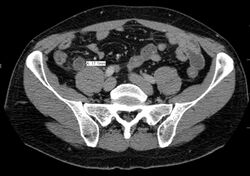

In children, the clinical examination is important to determine which children with abdominal pain should receive immediate surgical consultation and which should receive diagnostic imaging.[50] Because of the health risks of exposing children to radiation, ultrasound is the preferred first choice with CT scan being a legitimate follow-up if the ultrasound is inconclusive.[51][52][53] CT scan is more accurate than ultrasound for the diagnosis of appendicitis in adults and adolescents. CT scan has a sensitivity of 94%, specificity of 95%. Ultrasonography had an overall sensitivity of 86%, a specificity of 81%.[54]

Abdominal ultrasonography, preferably with doppler sonography, is useful to detect appendicitis, especially in children. Ultrasound can show the free fluid collection in the right iliac fossa, along with a visible appendix with increased blood flow when using color Doppler, and noncompressibility of the appendix, as it is essentially walled-off abscess. Other secondary sonographic signs of acute appendicitis include the presence of echogenic mesenteric fat surrounding the appendix and the acoustic shadowing of an appendicolith.[55] In some cases (approximately 5%),[56] ultrasonography of the iliac fossa does not reveal any abnormalities despite the presence of appendicitis. This false-negative finding is especially true of early appendicitis before the appendix has become significantly distended. Also, false-negative findings are more common in adults where larger amounts of fat and bowel gas make visualizing the appendix technically difficult. Despite these limitations, sonographic imaging with experienced hands can often distinguish between appendicitis and other diseases with similar symptoms. Some of these conditions include inflammation of lymph nodes near the appendix or pain originating from other pelvic organs such as the ovaries or Fallopian tubes. Ultrasounds may be either done by the radiology department or by the emergency physician.[57]

The accurate diagnosis of appendicitis is multi-tiered, with the size of the appendix having the strongest positive predictive value, while indirect features can either increase or decrease sensitivity and specificity. A size of over 6 mm is both 95% sensitive and specific for appendicitis.[62]

However, because the appendix can be filled with fecal material, causing intraluminal distention, this criterion has shown limited utility in more recent meta-analyses.[63] This is as opposed to ultrasound, in which the wall of the appendix can be more easily distinguished from intraluminal feces. In such scenarios, ancillary features such as increased wall enhancement as compared to adjacent bowel and inflammation of the surrounding fat, or fat stranding, can be supportive of the diagnosis. However, their absence does not preclude it. In severe cases with perforation, an adjacent phlegmon or abscess can be seen. Dense fluid layering in the pelvis can also result, related to either pus or enteric spillage. When patients are thin or younger, the relative absence of fat can make the appendix and surrounding fat stranding difficult to see.[63]